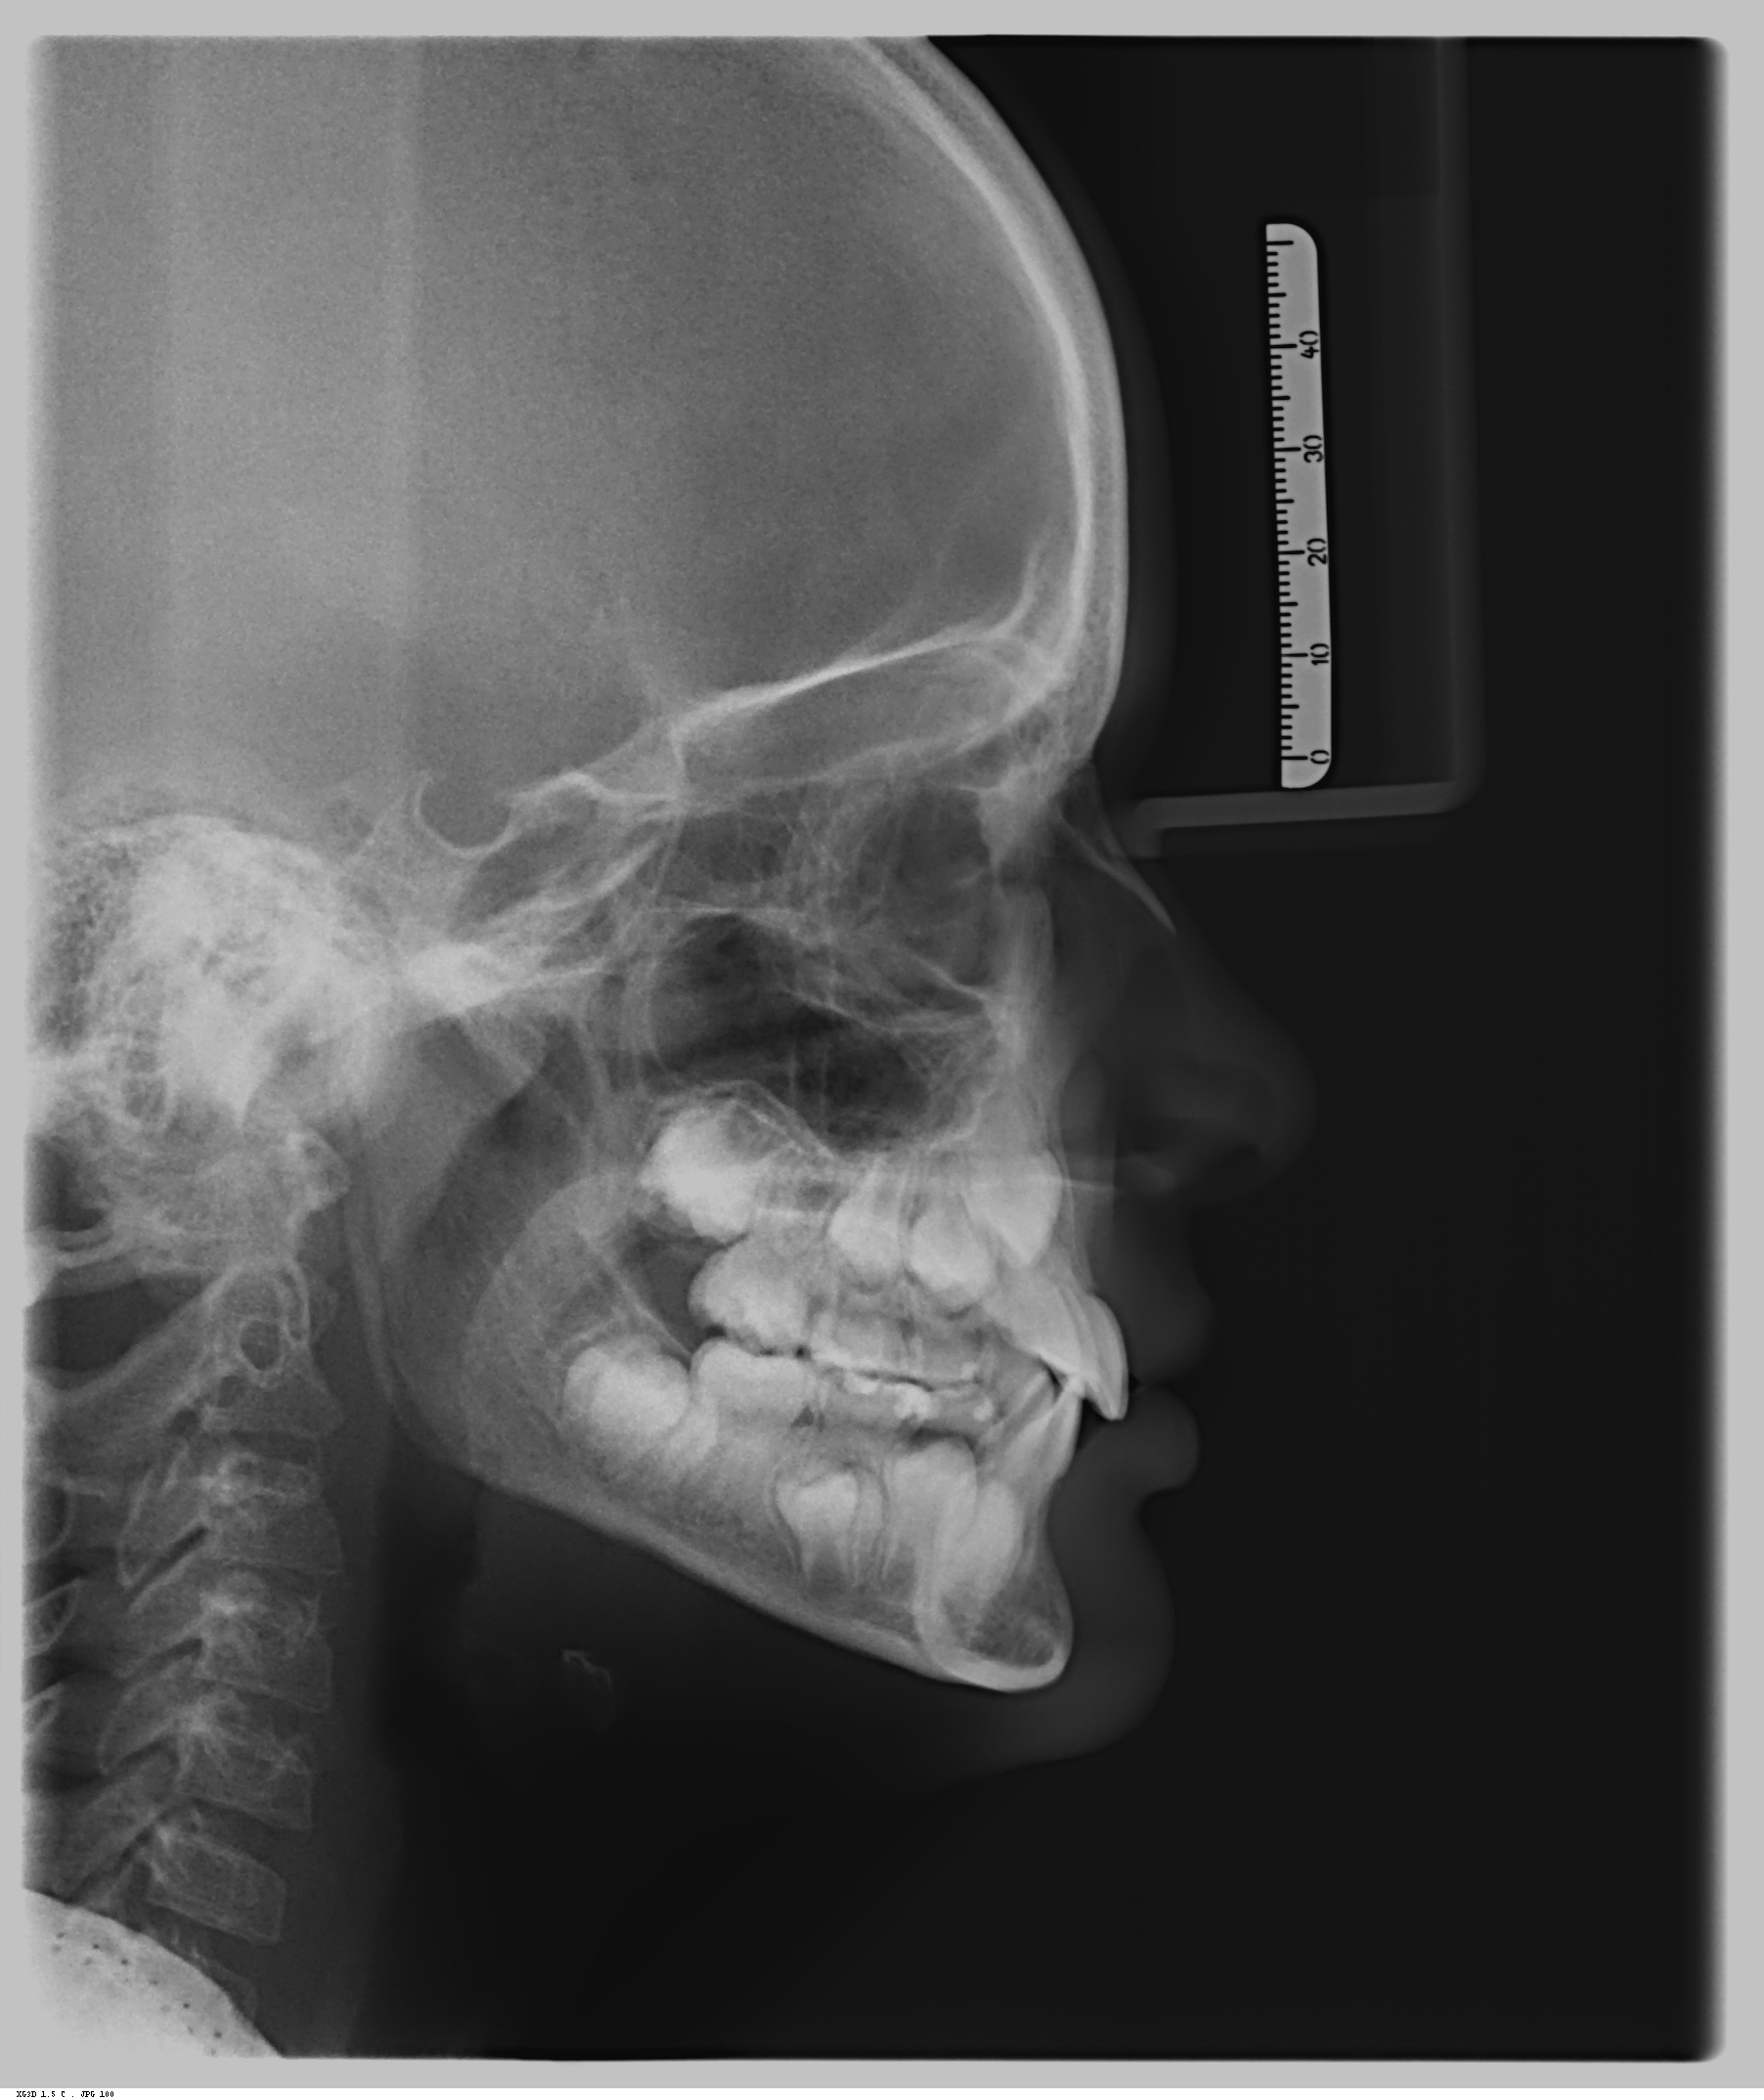

Telerradiografia Lateral

- Para o estudo do crescimento e desenvolvimento das anormalidades crânio-faciais.

- Para análises dos casos e diagnósticos.

- Para a avaliação progressiva da correção ortodôntica.

- Para o estudo das relações geométricas dento-faciais.

- Para análise funcional e determinação do tipo facial.